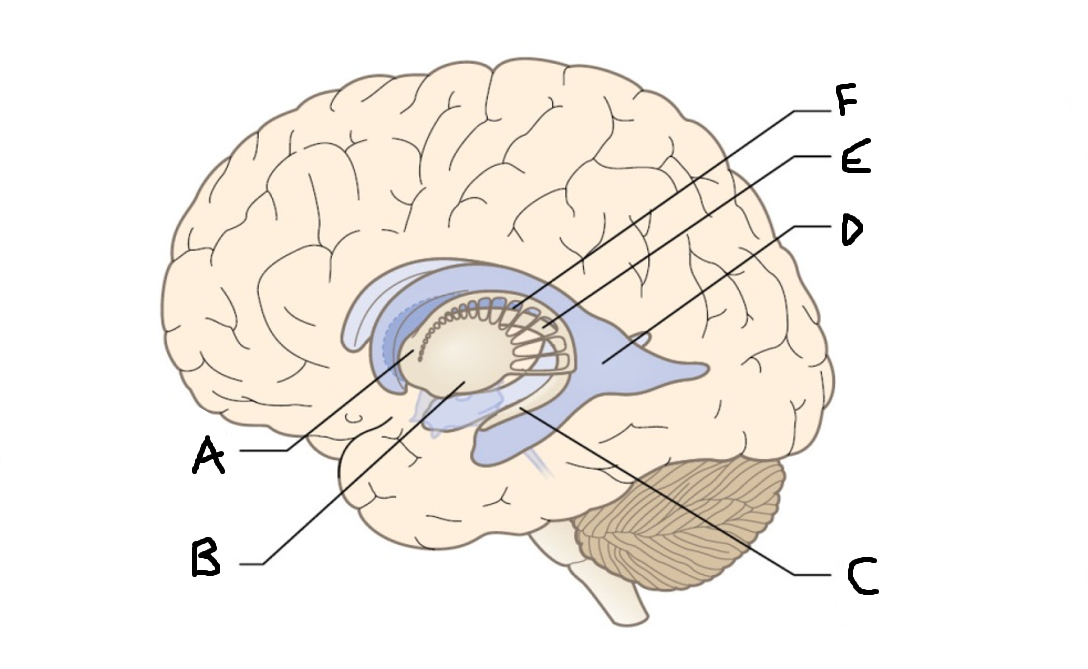

A

internal capsule (anterior limb)

B

caudate nucleus body

C

caudate nucleus head

D

putamen

E

caudate nucleus tail

F

thalamus

G

internal capsule (posterior limb)